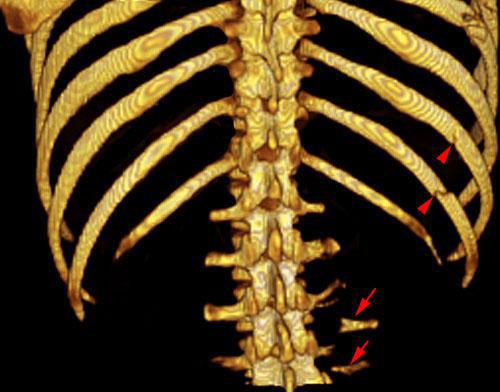

Estallido renal